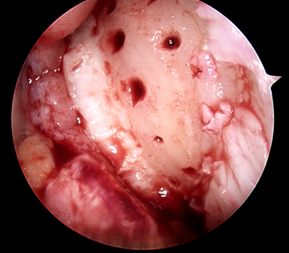

Microfracture is normally performed arthroscopically (through keyhole surgery). The first step is to identify the area of damage and assess its size, position and if the underlying bone is damaged as well. The loose or damaged cartilage is then cleared away leaving a bare bone surface.

Next, small holes are drilled or punched into the bone to create bleeding. The idea is for a blood clot to form and fill the area where the cartilage defect has occurred. The blood clot will then be gradually filled with cartilage producing cells that will replace the blood clot with cartilage. Normally this new cartilage is not as good as the original cartilage but will be better than having no cartilage there.

Cartilage injury identified

Step 2: damaged cartilage cleared

leaving bare bone

Step3:

Holes drilled in bone

Step 4:

Bleeding occurs from holes